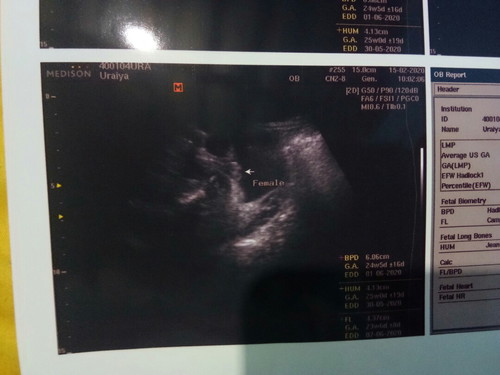

แบบนี้เพศอะไรค่ะแม่

หญิง หรือ ชายค่ะ

ตามใบซาวน์บอกเพศหญิง ดูแล้วน่าจะหญิงค่ะ

ลูกสาวค่ะ